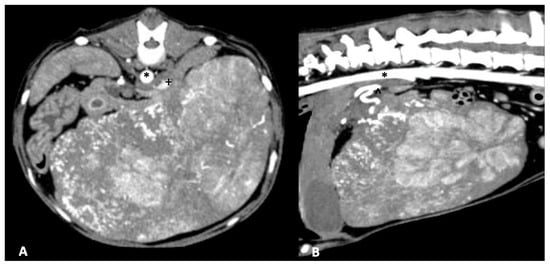

TAE and TACE have been evaluated in the treatment of canine hepatobiliary and prostatic tumors most commonly [98,99]. Embolization is the intravascular delivery of a device or materials, such as polyvinyl alcohol (PVA) or hydrogel polymers, to interrupt blood flow. Prior studies have validated the concept of intra-arterial drug infusions leading to higher concentrations in downstream tissues compared to intravenous infusions while sparing non-target tissues [100]. Drug eluting beads (DEB) are a novel method of TACE, providing a delivery system (beads) of chemotherapy in a sustained release form [101,102]. Potential benefits of DEB-TACE include lower systemic levels of chemotherapy (doxorubicin) in patients undergoing DEB-TACE compared to conventional TACE, which may enhance patient safety [103]. Evaluation of DEB with doxorubicin identified systemic doxorubicin levels that were unmeasurable 30 min after delivery within the tumor bed to stasis [104], and there was no systemic chemotherapy detected following deployment of DEB loaded with cisplatin into the left hepatic artery of normal dogs [105]. These findings demonstrate the substantial potential benefit in sparing systemic exposure of dogs to chemotherapy when treated with DEB-TACE. Clinical performance of DEB-TACE with doxorubicin in dogs with non-resectable HCC achieved stable disease (62%) or partial response (23%) at a median of 74 days following treatment. Minor and major complications occurred at a frequency of 26 and 11% respectively, and median survival time was 337 days [106]. Transarterial embolization and TACE for treatment of non-resectable hepatic tumors in dogs have been uncommonly reported [99,107,108,109] (Figure 3). The outcomes of two dogs with non-resectable HCC treated with TACE identified stable disease at 1 month, and progressive disease at 3 months, although superselection of tumor arterial supply was not achieved in either case [108]. In a separate report, TACE performed in four dogs with paclitaxel-containing embolic microspheres lead to a median tumor volume decrease of 42% at 1 month post treatment [109].

Figure 3. Transarterial embolization in a 13-year-old mixed breed dog. (A,B) An angiographic catheter has been placed in the hepatic artery and a direct angiogram of the hepatic tumoral blood supply has been performed. The liver tumor is delineated by a hashed line on both non-subtracted (A) and subtracted (B) angiographic images. (C) After embolization, the liver tumor is non-enhanced as the tumoral blood supply has been eliminated.